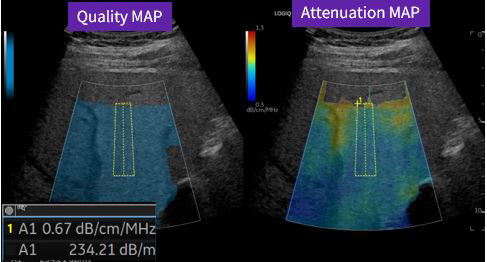

特長<3>

Ultrasound-guided attenuation parameter(UGAP)*

自動計測アルゴリズムにより最適な計測位置を自動判定し,主観によらない簡便で安定した計測をアシスト。